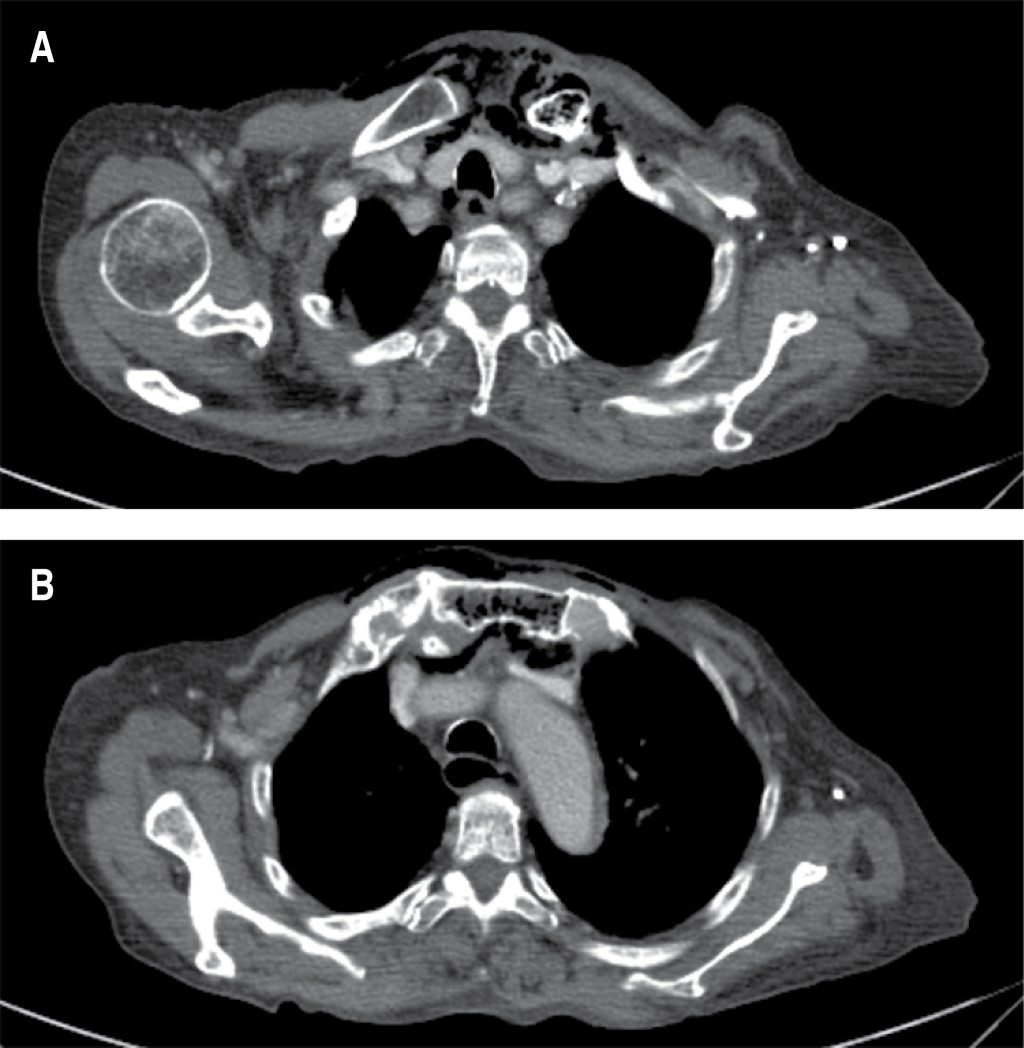

Durante el abordaje inicial en el servicio de urgencias, se decidió la colocación de sonda urinaria (la paciente aún tenía diuresis espontánea), con evidencia de piuria; se intentó colocar un acceso venoso central, palpando la presencia de enfisema subcutáneo, por lo que se solicitó realizar una tomografía computarizada; con reporte de un proceso inflamatorio localizado en la región cervical con extensión al mediastino superior, así como presencia de gas intramedular en clavícula izquierda y manubrio esternal, sugestivo de osteomielitis (Figuras 1 y 2). El estudio del líquido peritoneal obtenido a través del catéter de diálisis se encontró dentro de parámetros de referencia, por lo que ante la evidencia de choque séptico asociado a evidencia radiológica de mediastinitis Endo IIA, se propuso tratamiento quirúrgico urgente consistente en exploración y drenaje cervical, el cual no fue aceptado por los familiares de la paciente hasta 12 horas después del ingreso hospitalario. Se inició tratamiento antibiótico de amplio espectro (carbapenémico) desde el ingreso hospitalario y durante la cirugía se realizó un abordaje cervical en collar, 1 cm por encima de la escotadura esternal, se disecó por planos y se identificó presencia de líquido purulento proveniente de la articulación esternoclavicular izquierda; debido a la inestabilidad hemodinámica de la paciente, manifestada por hipotensión persistente, uso de aminas presoras con dosis progresivas y presencia de extrasístoles ventriculares, se decidió limitar la cirugía a control temporal del foco infeccioso con drenaje, irrigación y debridación parcial del área afectada.